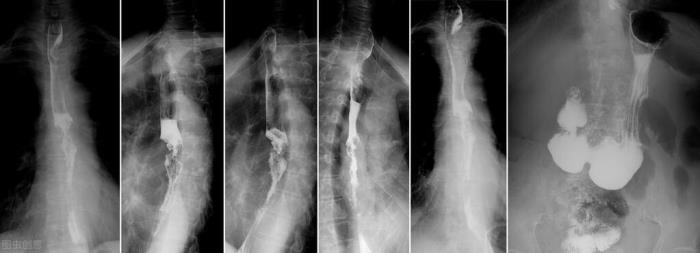

患者李XX,65岁,从去年开始总觉得喉咙不舒服,特别是吃馒头、煎饼等坚硬的食物时总感觉有东西被“挡”一下。老李常年患有咽炎,一开始认为是咽炎加重并未在意,过了三个月这种进食“阻挡感”明显加重,每次吞咽都能感觉到,甚至吃馒头时经常被噎住,还得用水“送”一下才能继续进食,由于吃面条喝稀饭并无不适,老李并没有寻医。又过了2个月,馒头已经咽不下去,吃面条也有了“阻挡感”,老李又拖了一个月才到医院就诊,医生听了老李的症状意识到这是典型的食管癌表现,做了钡餐及内镜最终被确诊为食管癌。

进行性吞咽困难警惕食管癌

老李的症状便是典型的进行性吞咽困难,即吞咽困难的症状随着时间推移越来越重,这是因为早期食道内肿瘤较小,对于吞咽的影响较小,随着肿瘤的不断增长,食道内的空间越来越“拥挤”,吞咽食团时阻挡感会变得越来越重,当肿瘤完全阻塞食道时,连喝水也变得困难起来。

所以当出现进行性吞咽困难时,一定去医院查个上消化道钡餐或者内镜检查,排除食管癌。